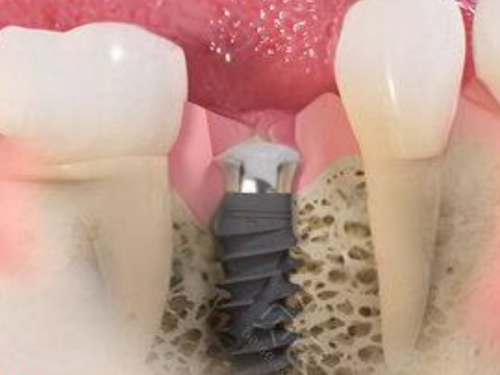

植入手术完成后,就进入了愈合期。这个阶段非常关键,因为种植体需要与牙槽骨进行骨结合,只有骨结合良好,种植体才能稳定地支撑后续的牙冠。愈合期一般需要3 - 6个月的时间,在此期间,患者可能需要佩戴临时义齿来修复部分咀嚼和美观功能。不同患者的愈合速度不同,所以愈合期的时间也会有所波动。

当骨结合完成后,就可以进行修复体的安装了。首先,医生会为患者取模,然后根据模型制作合适的牙冠。取模制作牙冠一般需要1 - 2周的时间,制作完成后,医生会将牙冠安装在种植体上,至此,种植牙手术基本完成。安装牙冠后,患者就可以正常使用种植牙进行咀嚼了。